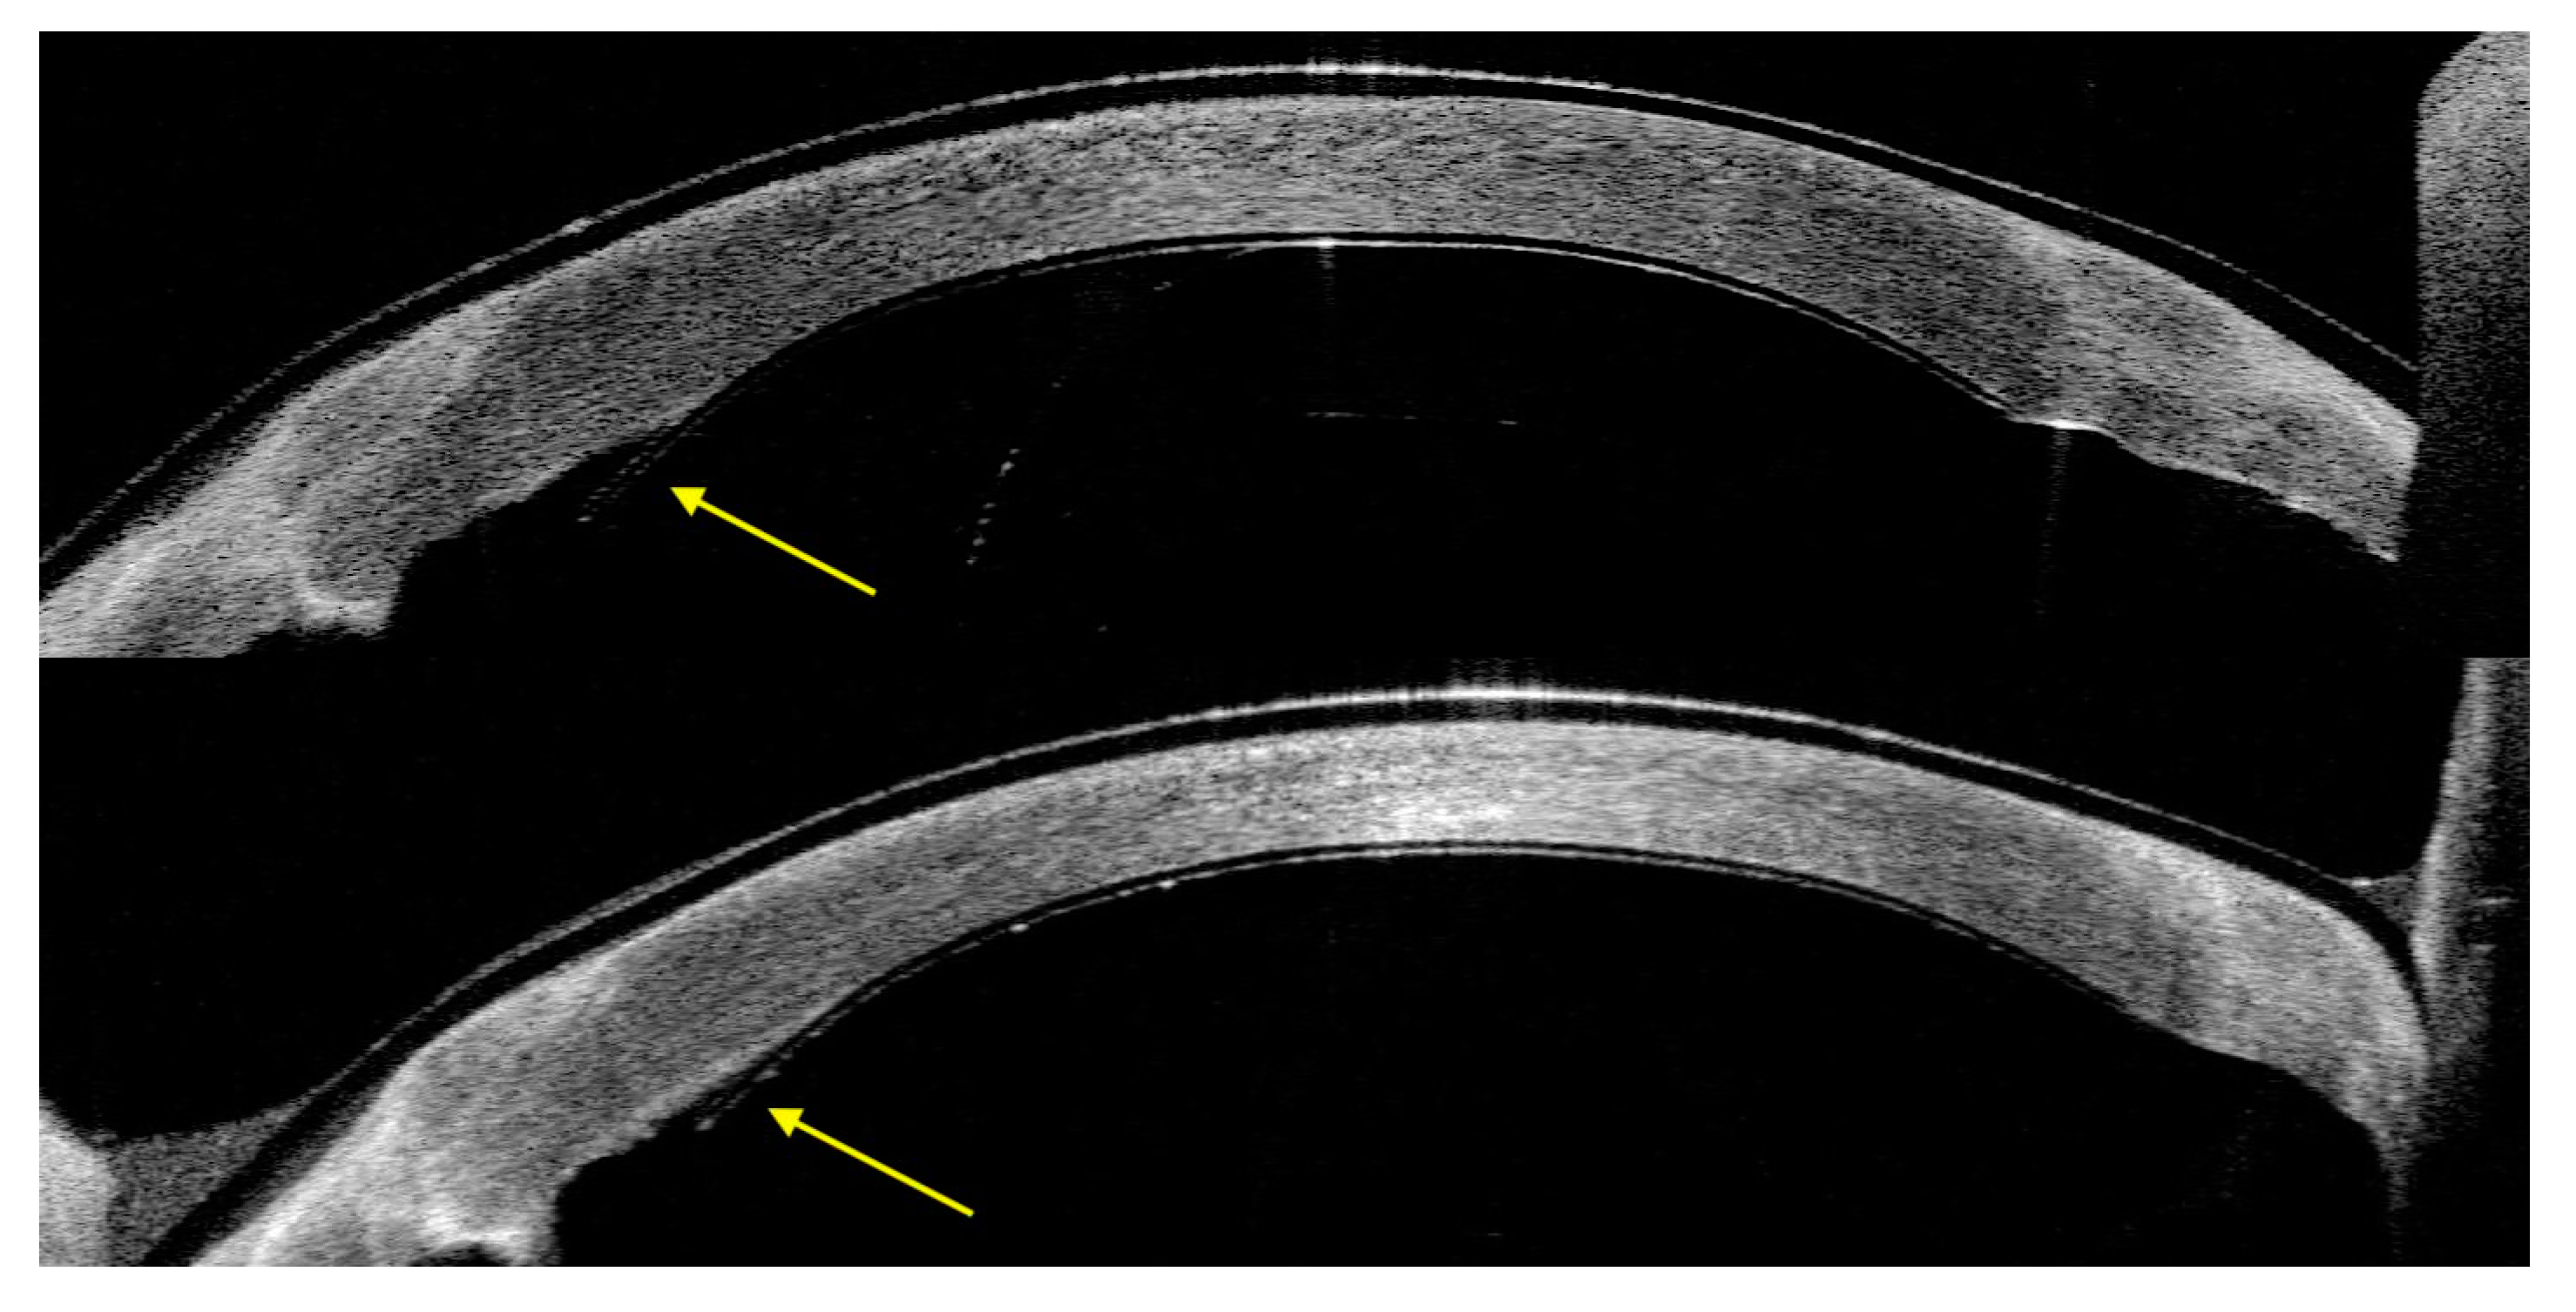

In Case 1, AS-OCT showed a quick resolution of the posterior stromal ripples at day 2 post-operative. Additionally, a small peripheral inferior nasal detachment of the device, from 6 to 8 o’clock, at the level of PK graft–host junction was noticed at day one, which was stable during the follow-up (Figure 4).

Figure 4.

Case 1. Small detachment of EndoArt (yellow arrow), which became stable over time (day 2 on top versus 3 months at bottom).